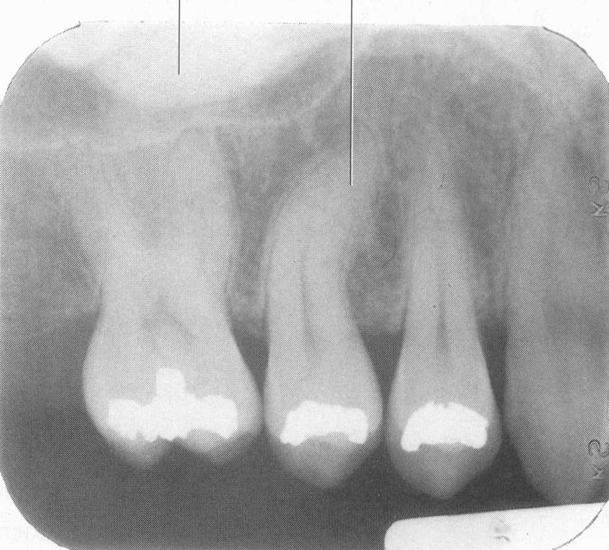

Dilaceration